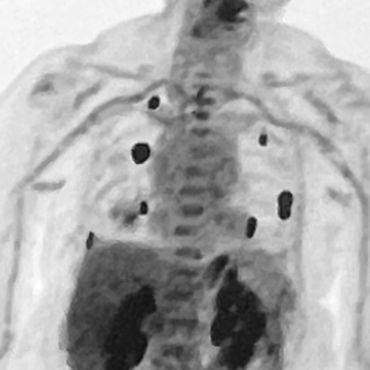

Images from her scans are below. Had her scans came back with little to no improvement, I was prepared to begin in-depth research on ivermectin and fenbendazole. Researching these along with the above items on X shows interesting results.

On Sept 17th, my mom had her second pet scan. Later that night the nurse practitioner called with very good news. She stated she was very pleased with the results and did not want my mom to come in for her fourth immunotherapy session the next day. The nurse stated she needed to get with the provider to ensure they will continue with the treatments. While this was very good news, we never saw the scan results and unfortunately were left hanging with this information.

On Oct 15th, we finally met with the oncologist. He stated there were "no active disease" and he showed us multiple images and scans and simply said we do not see anything. I asked the doctor, why the first oncologist she met with said this cannot be cured and would not go away and if these results were typical? His response was something along the lines that there is more data about immunotherapy in the last 10 years and they are seeing better success stories. However, the wording in her actual report was "showed remarkable response". We never once mentioned anything about my mom's strict diet.